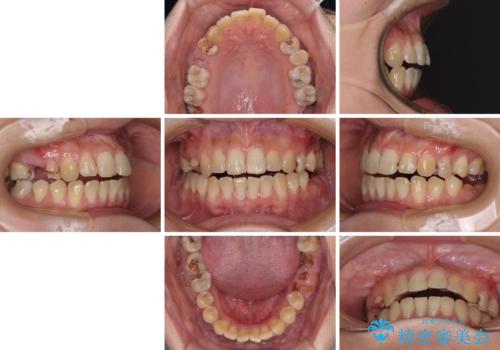

- 奥歯に問題が多くて困っているとのことで来院された患者様です。

開咬により奥歯のみが接触している状態で、前歯部にほとんど接触のない状態で、奥歯に非常に負担のかかる咬み合わせでした。

また、欠損や根管治療の必要な歯など、むし歯による問題も多く散見されました。

まずはむし歯の治療を行い、その後ワイヤー矯正にて咬み合わせを改善し、途中インプラント埋入を行い、矯正治療後に補綴治療を行うこととしました。